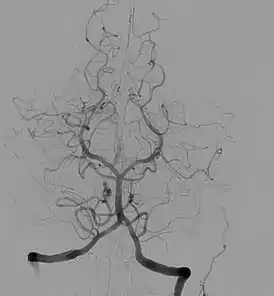

Ангиография показывает функциональное состояние сосудов, окольного кровотока и протяжённость патологического процесса. Исследование позволяет выявить повреждения и пороки развития кровеносных сосудов: аневризмы, сужения сосудов, мальформацию, нарушения проходимости сосудов (атеросклероз, тромбоз), а также повреждения и пороки развития различных органов, опухоли. Например, ангиограмма сосудов головного мозга со специфической картиной помогает диагностировать болезнь моямоя.